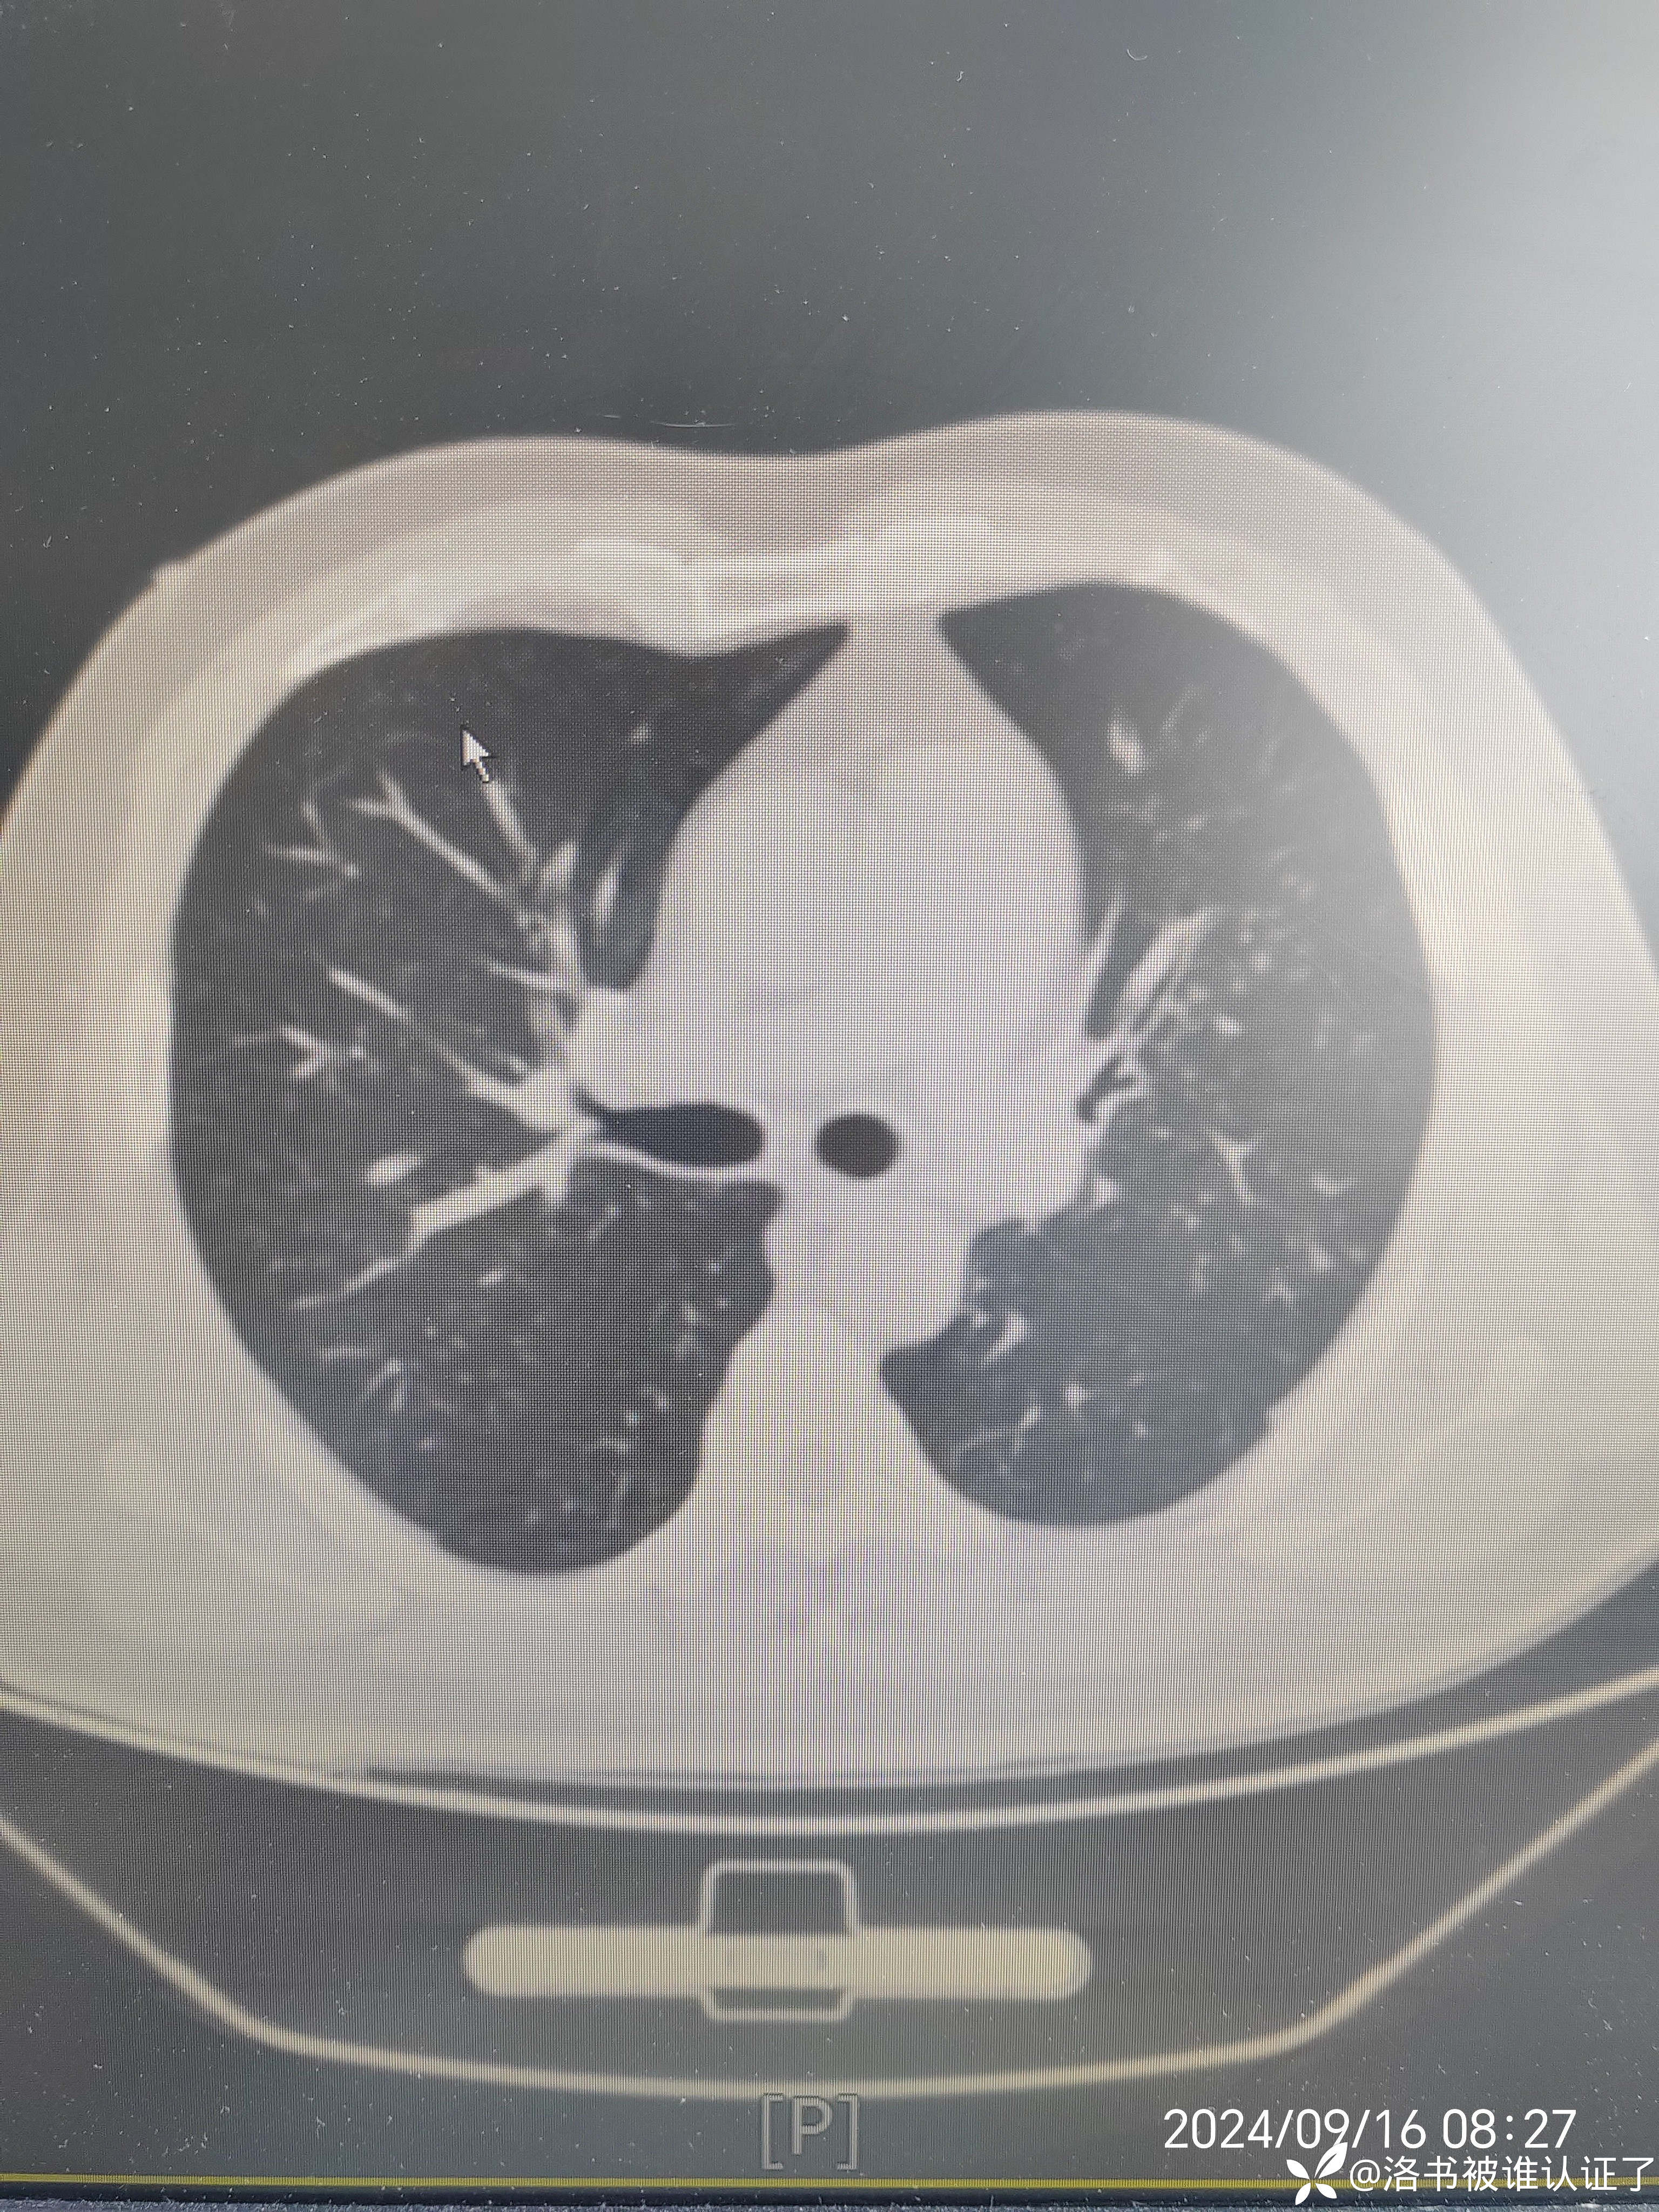

【检查】胸部CT示肺炎。

【临床诊断】:肺炎